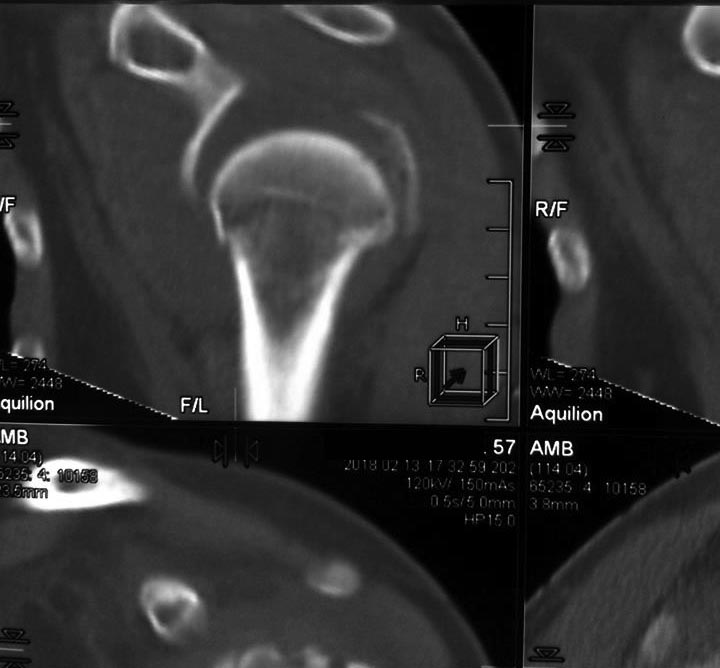

Перелом проксимального метаэпифиза плеча

Травма 10 дней назад, падение при катании на обычных лыжах. Сама врач-рентгенолог 57 лет.

Левая рука, недоминатная. На данный момент ходит в косынке, вся в сомнениях, что делать.

Мнения по лечению: - ничего не делать - остеосинтез пластиной блокированной - первичное эндопротезирование (в наличие только геми, delta не потянет) Может кто-то что более дельное предложит.